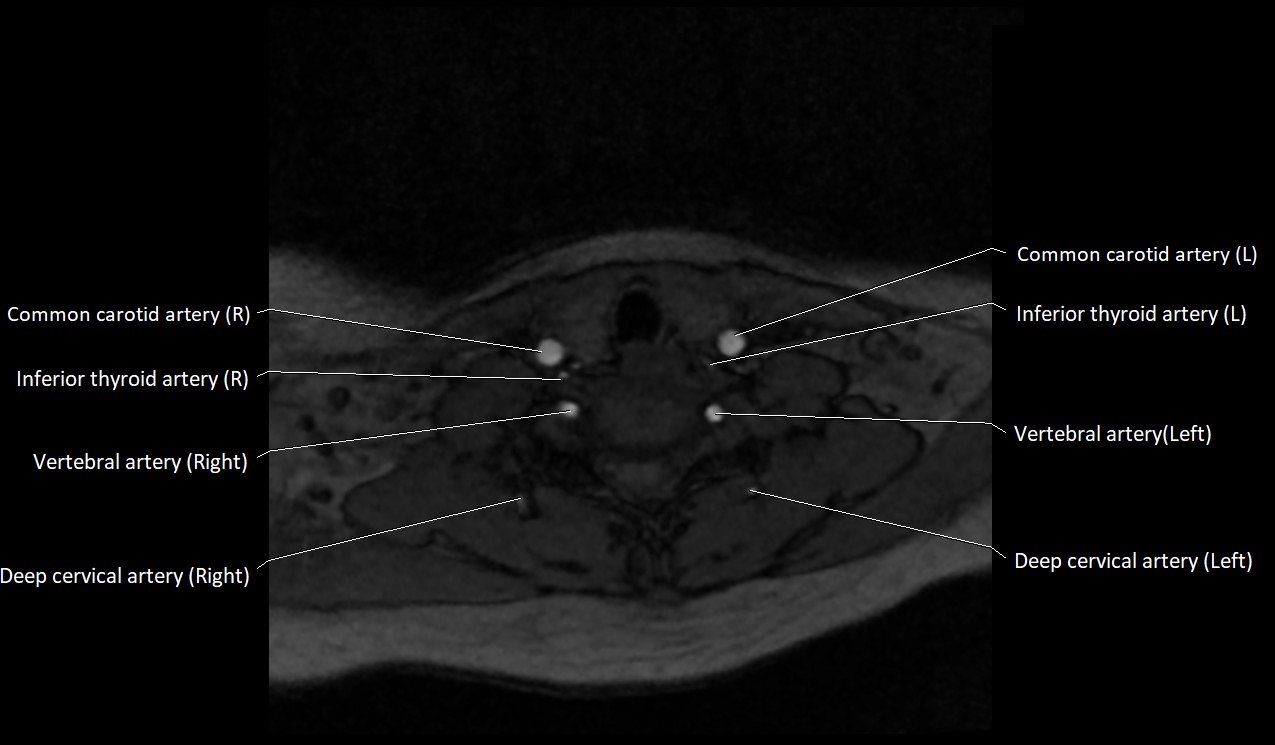

MRI images

image